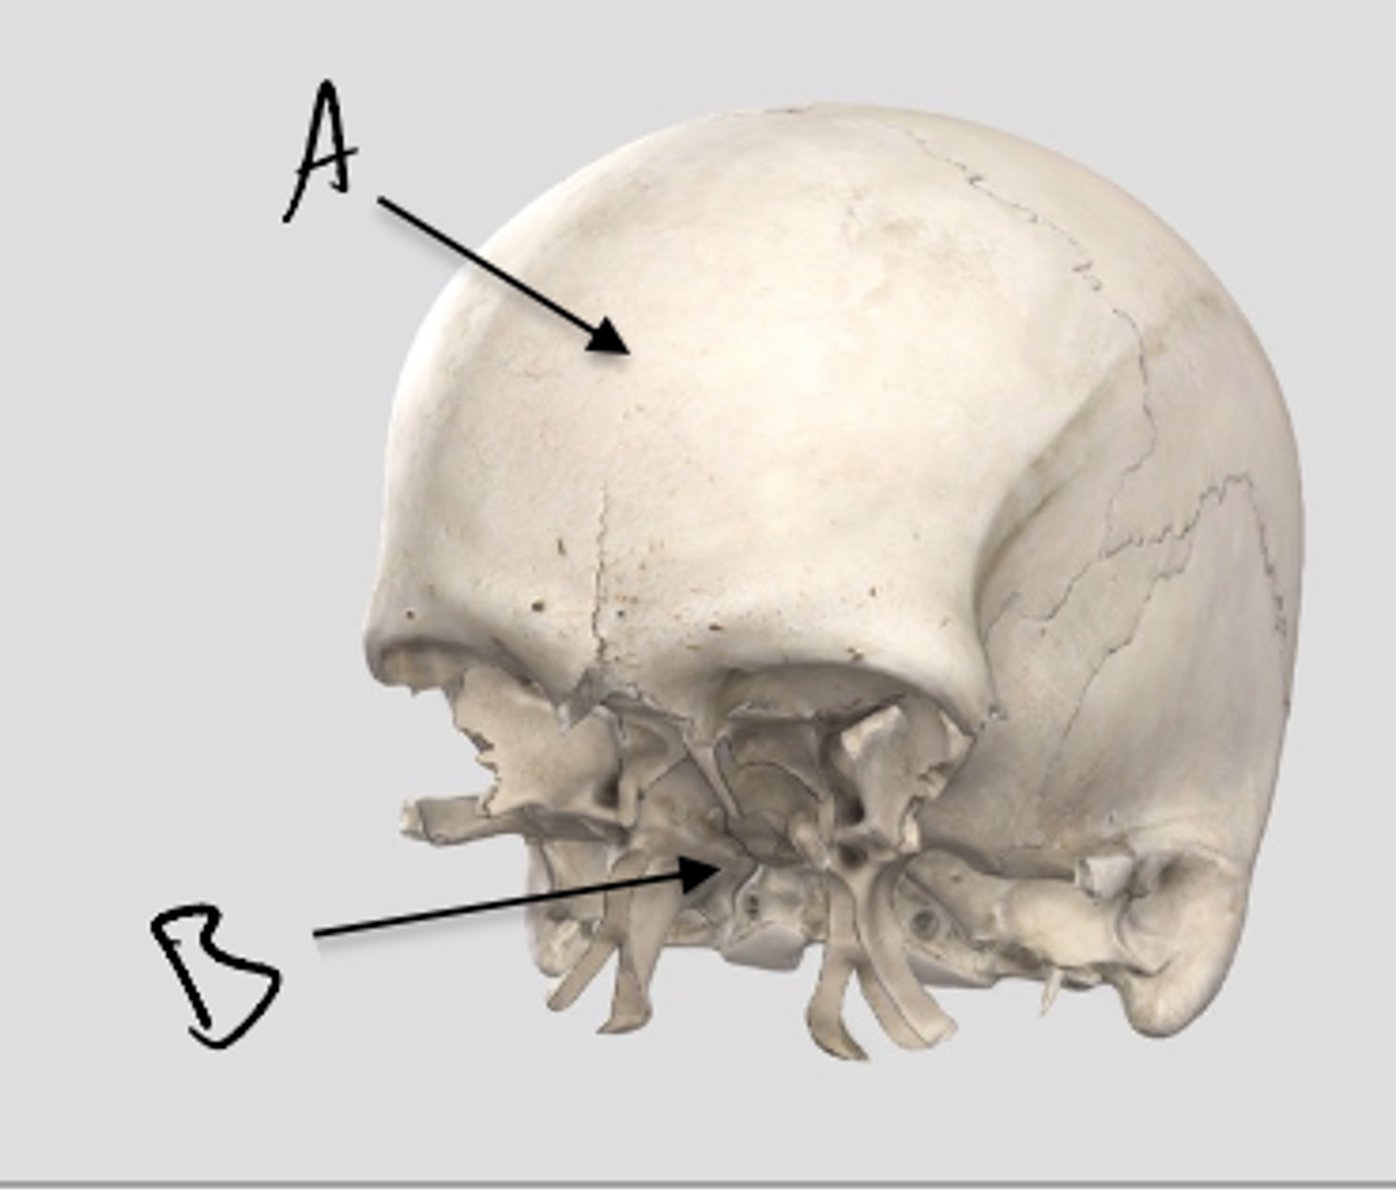

A. SES

B. MSS

C. SOS

knowt flashcard image